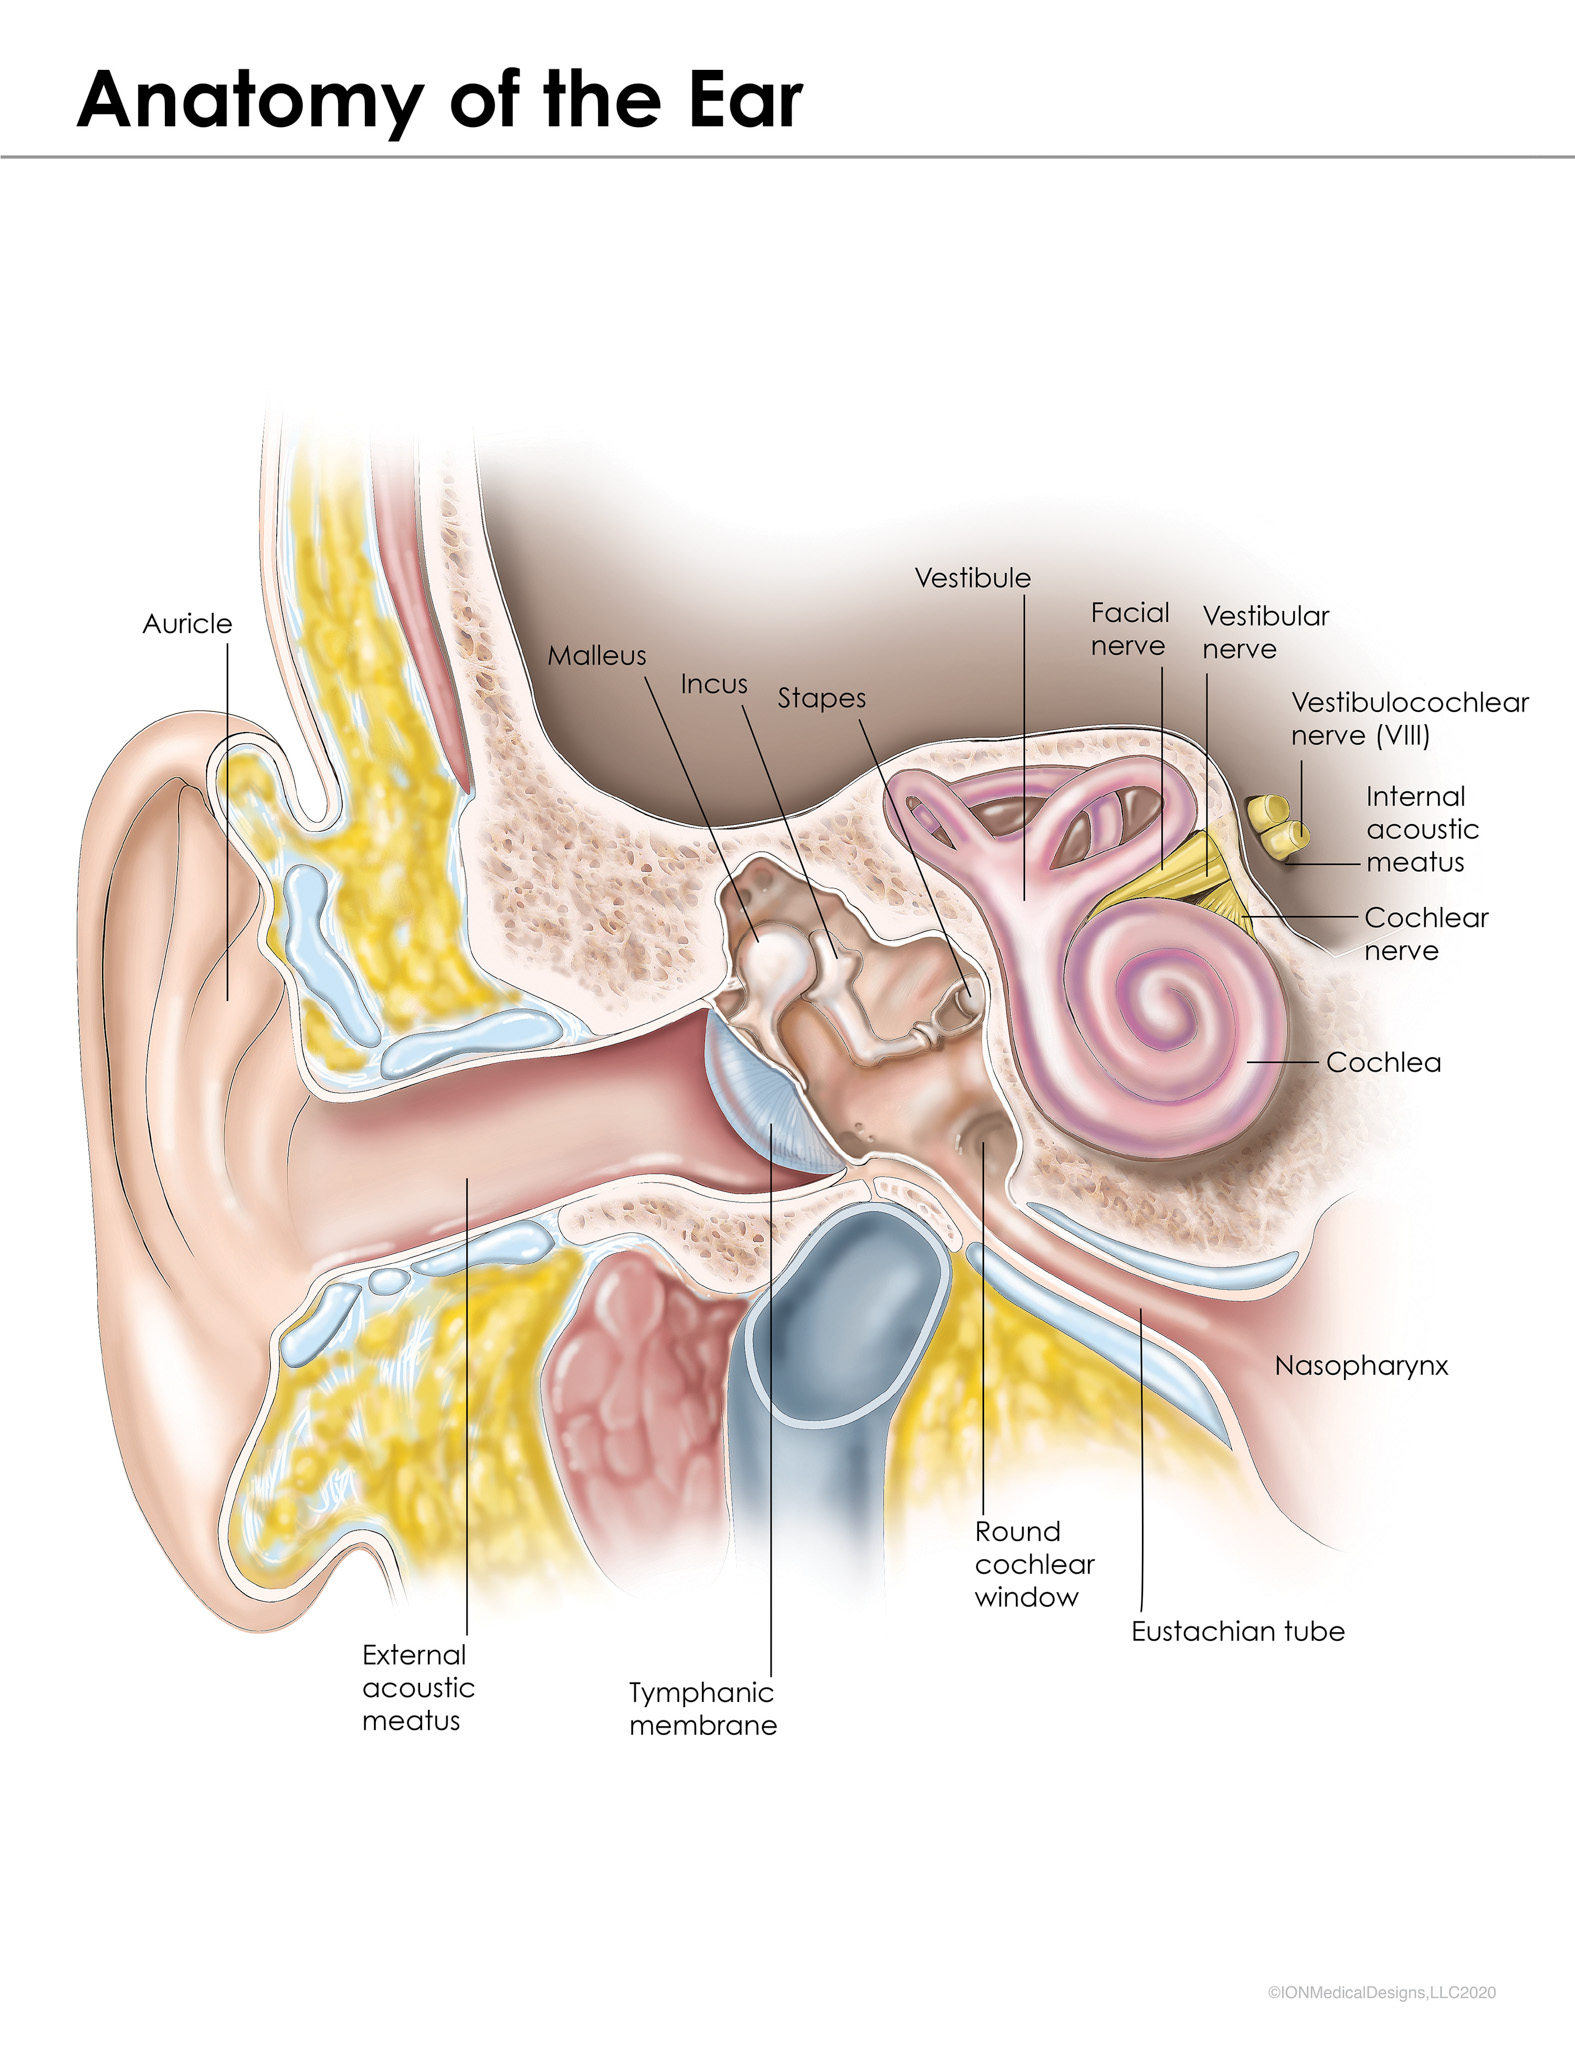

I create medical illustrations, animations, interactive projects and timelines for physicians, attorneys, medical device and pharmaceutical companies to create illustrations for educational purposes.

I am proud to educate people. To scientifically visualize what’s unseen by the naked eye for the general public!